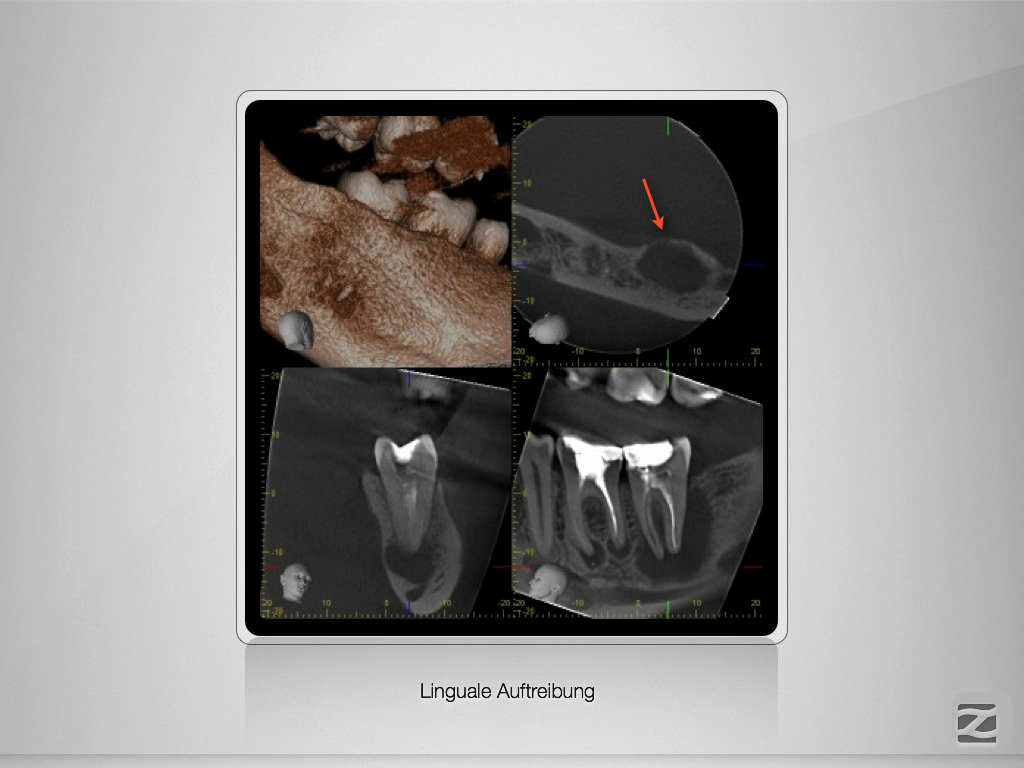

37D.003

Ausgedehnte apikale Lyse